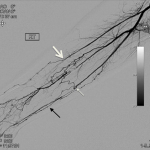

DIGITAL SUBTRACTION ANGIOGRAPHY (DSA)

The following gallery shows examples of Buerger disease seen on DSA studies. Click the thumbnails below to open up the gallery.